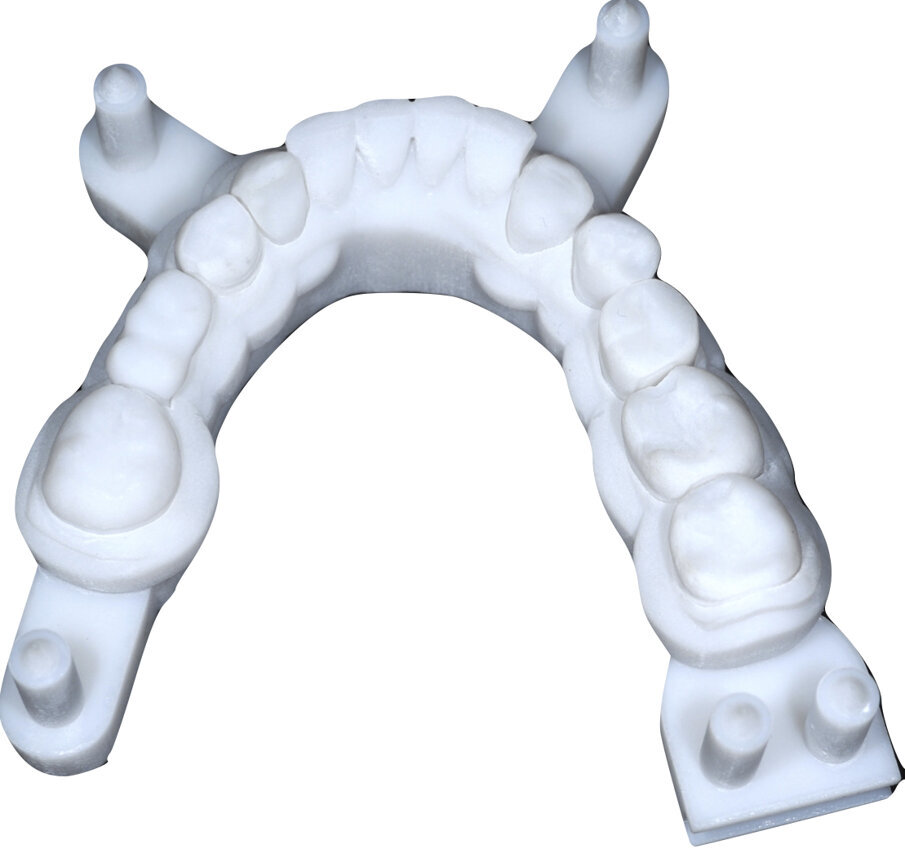

Si esegue perciò cefalometria (Fig. 8) su radiografia latero-laterale (Fig. 9) e axiografia dei movimenti limite (Cadiax Compact, Gamma Dental) (Fig. 10) per la programmazione di un articolatore a valori medi (Artex TR, AmmanGirrbach) e montaggio dei modelli con arco faciale, che confortano nella produzione di un primo provvisorio prelimatura con rialzo arbitrario della VDO di 5 mm sull’asta incisale e miglioramento di OB e OJ, a scopo pre-terapeutico interlocutorio e di immediata risoluzione estetica. Conclusa la necessaria terapia causale e restaurativa viene eseguita la scansione intraorale delle arcate (TRIOS 3 Pod, 3Shape) (Figg. 11-14) e del rapporto articolare con cera di RP (Fig. 15). La scansione è stampata (VisiJet RWT, 3D Systems) con monconi sfilabili tramite stampante 3D (ProJet MJP 2500 Plus, Selltek) (Figg. 16-20), i modelli derivanti sono zoccolati e montati con cere di RP e arco faciale su articolatore a valori individuali (Reference SL, Gamma Dental). La programmazione dell’articolatore derivante dalla registrazione axiografica è ora eseguita come da indicazioni del software (Gamma Dental software, sia per l’uso degli inserti condilari ed incisali, sia per la definizione degli angoli di SCI e di Bennet (Fig. 21). Lo spazio protesico risultante a una VDO adeguata alla riabilitazione dei denti anteriori vitali, con anatomia non ulteriormente modificabile, è insufficiente per uno stabile ripristino dei rapporti occlusali, specie nei tragitti funzionali. Si decide perciò di impiegare due inserti rossi di programmazione di protrusiva (+2 mm) per riposizionare la mandibola in TRP (Figg. 22, 23).

Ciò consente un miglioramento dei rapporti interarcata, un guadagno di spazio protesico in regioni premolari e molari, ed il mantenimento di uno spazio protesico conforme ad una corretta anatomia per i denti vitali da 1.3 a 2.3. Al paziente viene pertanto aggiornato il piano di trattamento e proposta la riabilitazione in TRP, con la previsione di overlays all’arcata inferiore per costruzione del nuovo piano occlusale. In posizione terapeutica sono modellati i coni delle centriche attive sui monconi sfilabili all’arcata inferiore, per la successiva individuazione al CAD con modulo articolatore del piano occlusale studiato. Questo rapporto articolare in TRP è ora scansito con scanner da laboratorio Xanos Evo Scan Compact (Fig. 24).

I modelli sono così importati in corretta posizione spaziale tramite il modulo exocad Virtual Articulator (Fig. 25). Non avendo a disposizione nel CAD l’analogo virtuale dell’articolatore Reference SL, viene impostato il sistema virtuale SAM, che usa lo stesso piano di riferimento axio-orbitale e geometria sovrapponibile al Reference SL. Per la programmazione virtuale dei parametri funzionali dell’articolatore si riesegue l’output dall’axiografia elettronica con Gamma Dental per SAM (Fig. 26). Si procede perciò ora con la modellazione CAD della ceratura mantenendo il riferimento dato dal piano occlusale individuato dai coni di centrica scansiti con l’articolatore (Fig. 27). L’articolatore virtuale consente una prima verifica dei rapporti occlusali tra gli elementi e un abbozzo di funzionalizzazione delle cuspidi con strumenti virtuali dinamici, che permette di arrivare ad un CAD design vicino alla morfologia ricercata (Figg. 28-33). Il modellato è ora fresato in cera Yeti Dental al CAM con fresatore VHF Cam5-S1 ed i denti in cera, tutti singolarmente sfilabili, sono posizionati sui modelli eseguiti con stampa 3D.